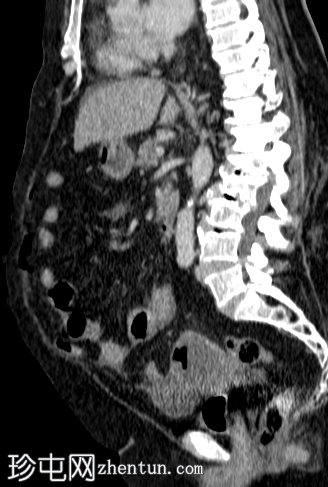

轴位增强扫描(门静脉期)

宫腔内可见气液平面,符合子宫蓄脓(宫腔内有脓液)。子宫前壁裂开,多个宫外气体灶延伸至腹膜外和腹膜内间隙,提示子宫穿孔。同时可见少量盆腔腹水和少量盆腔脂肪条索状改变。

其他发现:左侧附件囊肿、胆结石、双侧少量胸腔积液。